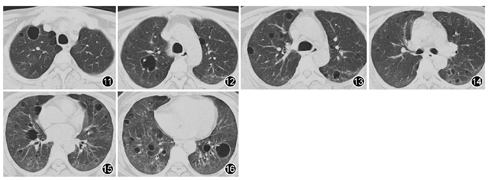

患者为中年女性,工作环境潮湿可能存在霉变,影像学表现可见双肺弥漫多发囊腔影并磨玻璃密度改变,纵隔淋巴结增大,实验室检查发现ESR明显增快,球蛋白增加,白蛋白降低;类风湿因子明显增高,依据其临床症状、体检、实验室检查及肺组织活检病理,经呼吸科与风湿病科会诊讨论考虑为原发性干燥综合征(primary Sjögren′s syndrome, pSS)。于2015年11月19日给予甲泼尼龙琥珀酸钠40 mg,1次/d,静脉滴注22 d后改为口服泼尼松片45 mg,1次/d;并于2015年11月21日联用环磷酰胺200 mg,1次/2 d,静脉滴注,口服来氟米特片10 mg、硫酸羟氯喹片200 mg及白芍总苷胶囊600 mg,2次/d,患者病情控制良好,于2015年12月15日出院,出院时咳喘症状明显减轻,复查胸部CT可见双肺弥漫磨玻璃影明显变淡,空腔似有缩小(图11、图12、图13、图14、图15、图16),总体变化不大。